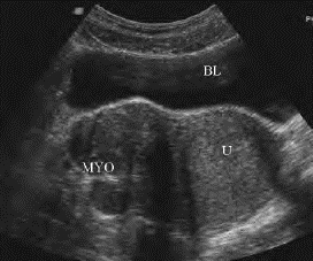

1.37.5五、非先天性子宫疾病

-